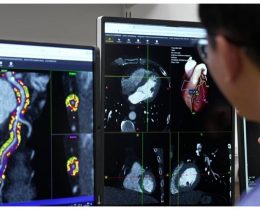

Doceree has announced the integration of its AI-powered solution, Spark, with Oracle Health (formerly Cerner) to enhance healthcare professional...

Artificial intelligence is transforming how patients first engage with the healthcare system, shifting from traditional in-person or phone-based...